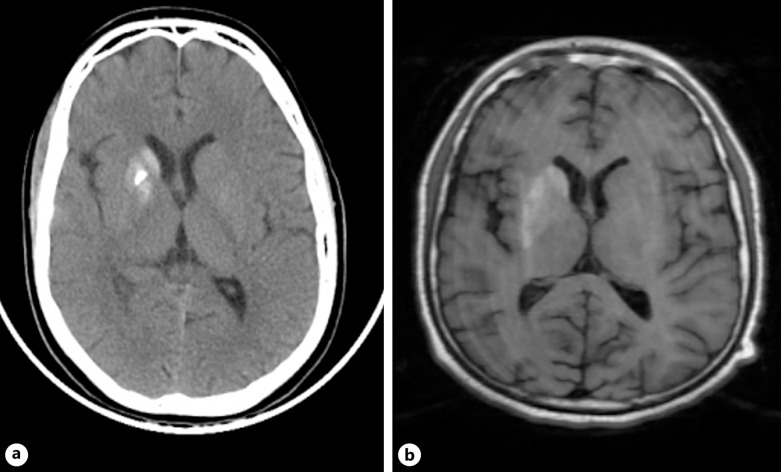

Case presentation: We report a 17-year-old male with poorly controlled type 1 diabetes mellitus presenting with left-sided hemichorea-hemiballismus of acute onset associated with hyperglycemia without ketoacidosis. Brain imaging revealed increased attenuation in the right caudate and putamen on CT and hyperintensity on T1-weighted MRI, consistent with diabetic striatopathy. The abnormal movements abated after 1 month through dietary counseling, increased insulin dosage, and anti-chorea therapy.